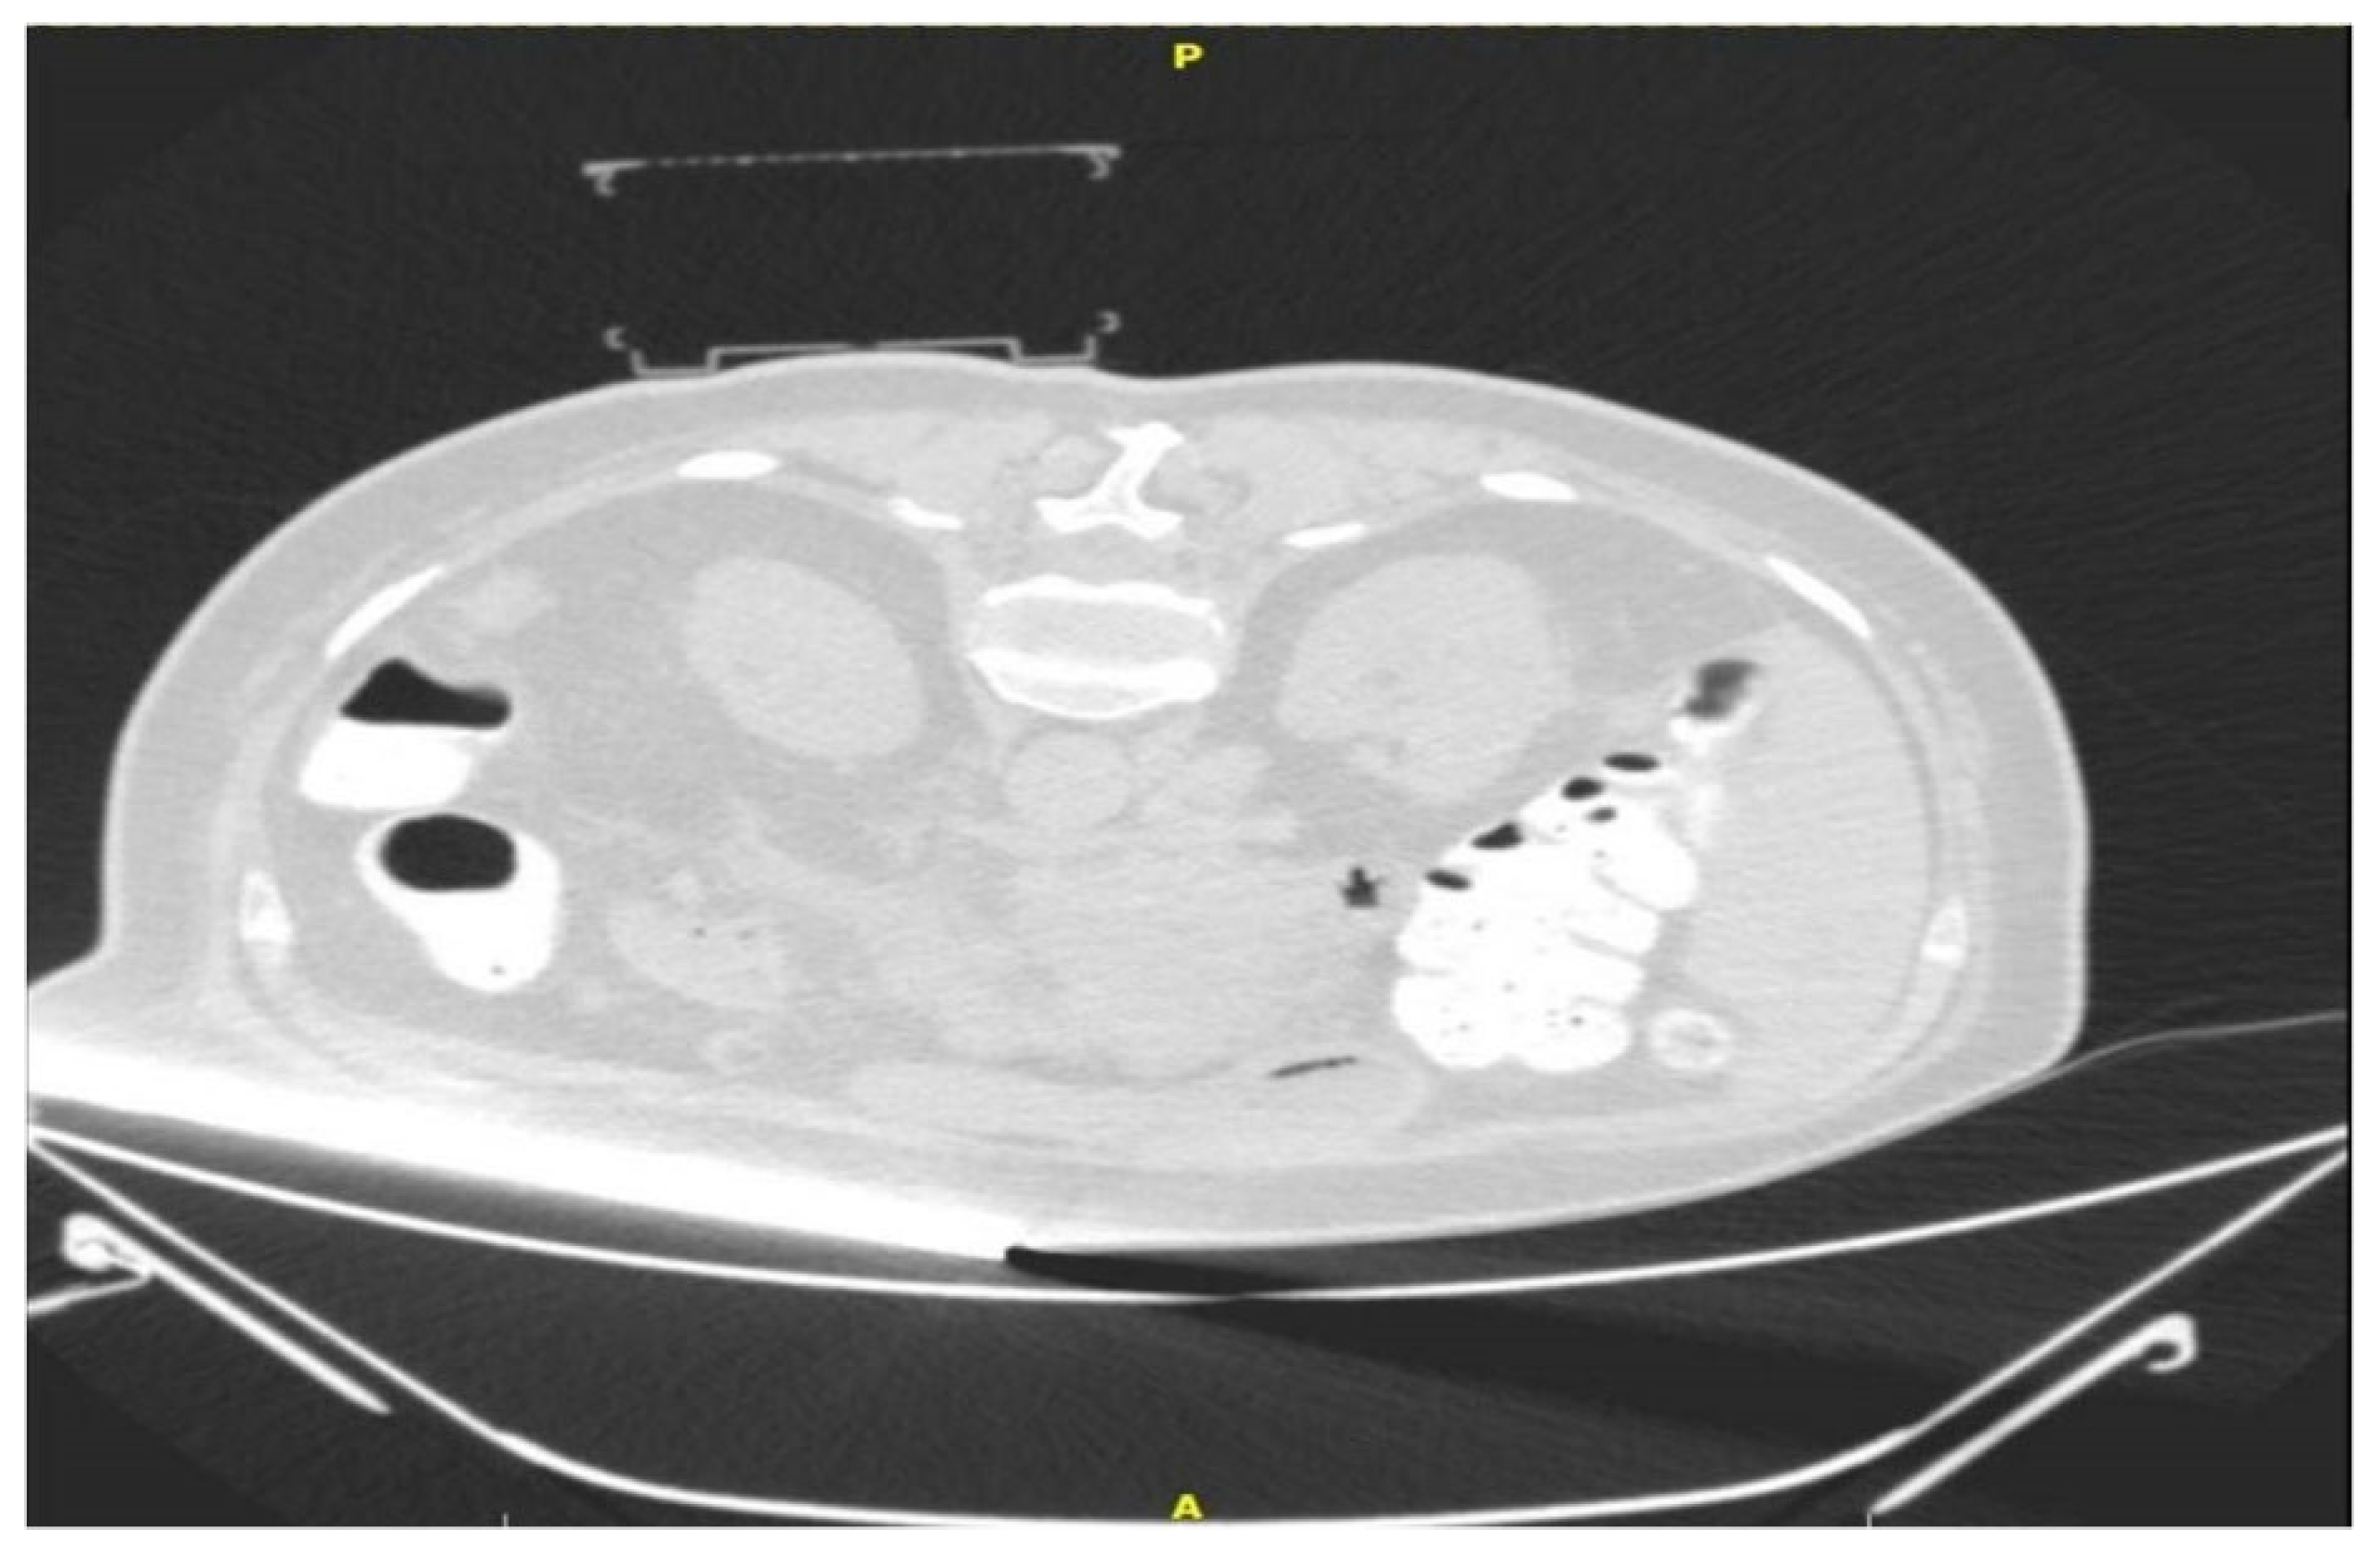

Figure 2. Initial CT scan with target and the cube mounted on the skin.

The “CNS” (Medical Templates AG, Egg, Zurich, Switzerland) was described recently in detail in an ex vivo study [3]. In short, the PC is a disposable cube-shaped apparatus consisting of an upper- and a lower-grid template, with fields marked both with letters and numbers (e.g., field B2). This cubic-shape apparatus will collapse during a puncture if the needle is too short, or if the needle path needs to be adjusted. The pre-mounted adhesive on every foot of the cube allows for fixation on the skin of the patient. The PC consists of polypropylene, which is hyperdense on CT planning scans (approx. −200 Hounsfield units) (Figure 2).

The CT images are sent to the dedicated software “Synedra View Professional” (Synedra information technologies GmbH, Innsbruck, Austria) via PACS. The software recognizes the location of the PC on the patient’s skin, and a virtual model of the cube is created. Then, 3D MPR reconstructions and a virtual needle path are used by the operator for selection of target approach through the PC. Once a path is chosen, the corresponding holes on both the upper and lower surfaces are indicated by green dots on the virtual cube, as well as in the 3D MPR view. As the virtual needle has distance markers, using puncture needles with distance indicators allow for control of the puncture depth (Figure 3A). To achieve accuracy in the insertion of the puncture needle, the software automatically places the path of the virtual needle in one corner of the indicated hole. Next, the operator introduces the puncture needle into the determined coordinates on both layers of the PC. Sequential control scans are performed until the needle reaches the target.